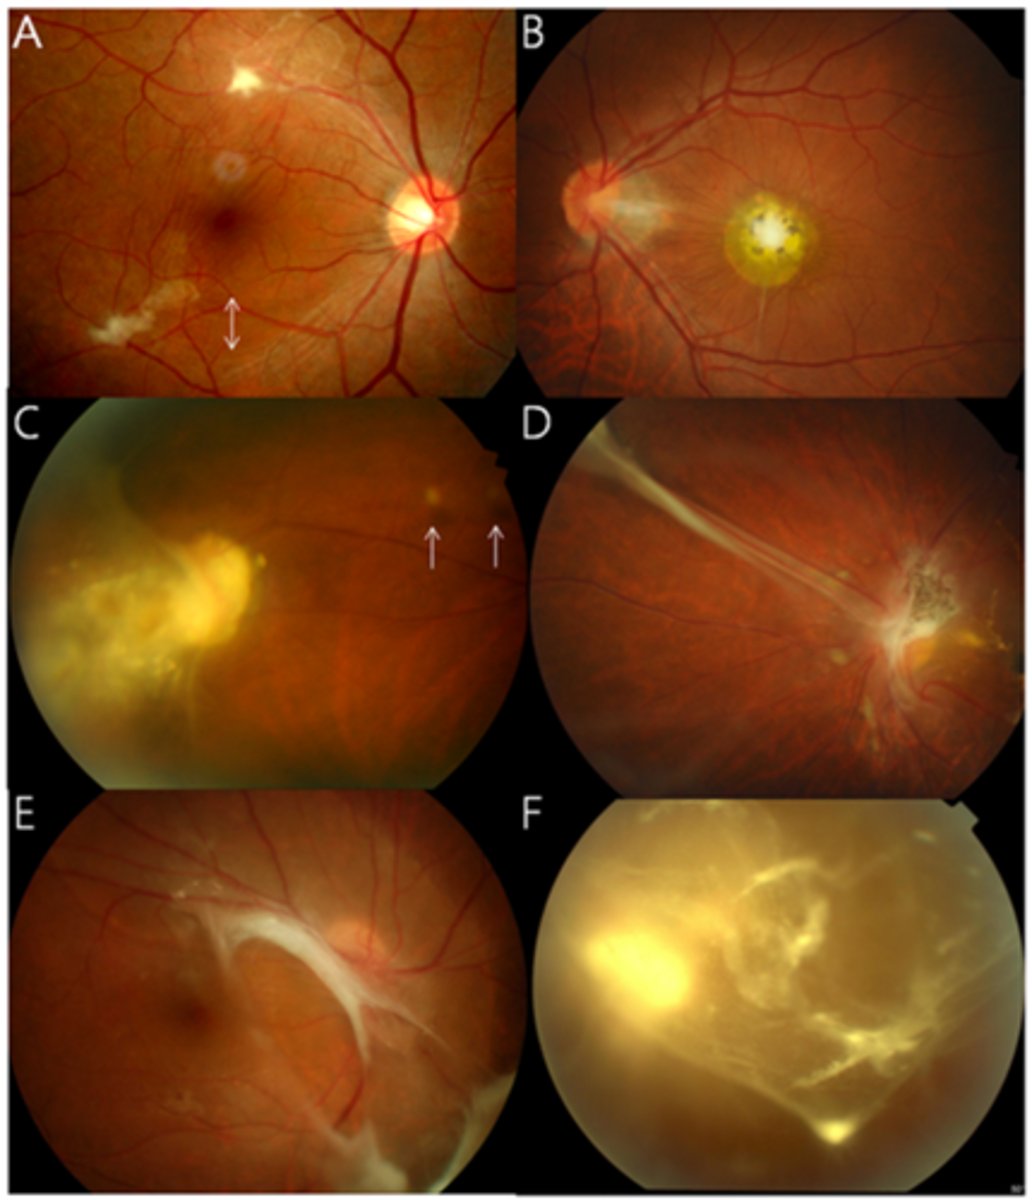

What finding of toxoplasmosis is seen in A/B?

retinitis turns into hazy scar with nerve pallor

What finding of toxoplasmosis is seen in C/D?

scarring overtime with VA loss/scotoma

What is seen in toxoplasmosis with OCT?

acute = retinitis = inflam, thickening of layers

acute = vitritis = dots and haze vitreous

chronic = necrotizing atrophy = scarring, thinning

What findings of toxoplasmosis are seen here?

retinal vasculitis

exudative scar

focal, hazy vitritis and retinitis

What findings of toxoplasmosis are seen here?

latent scars